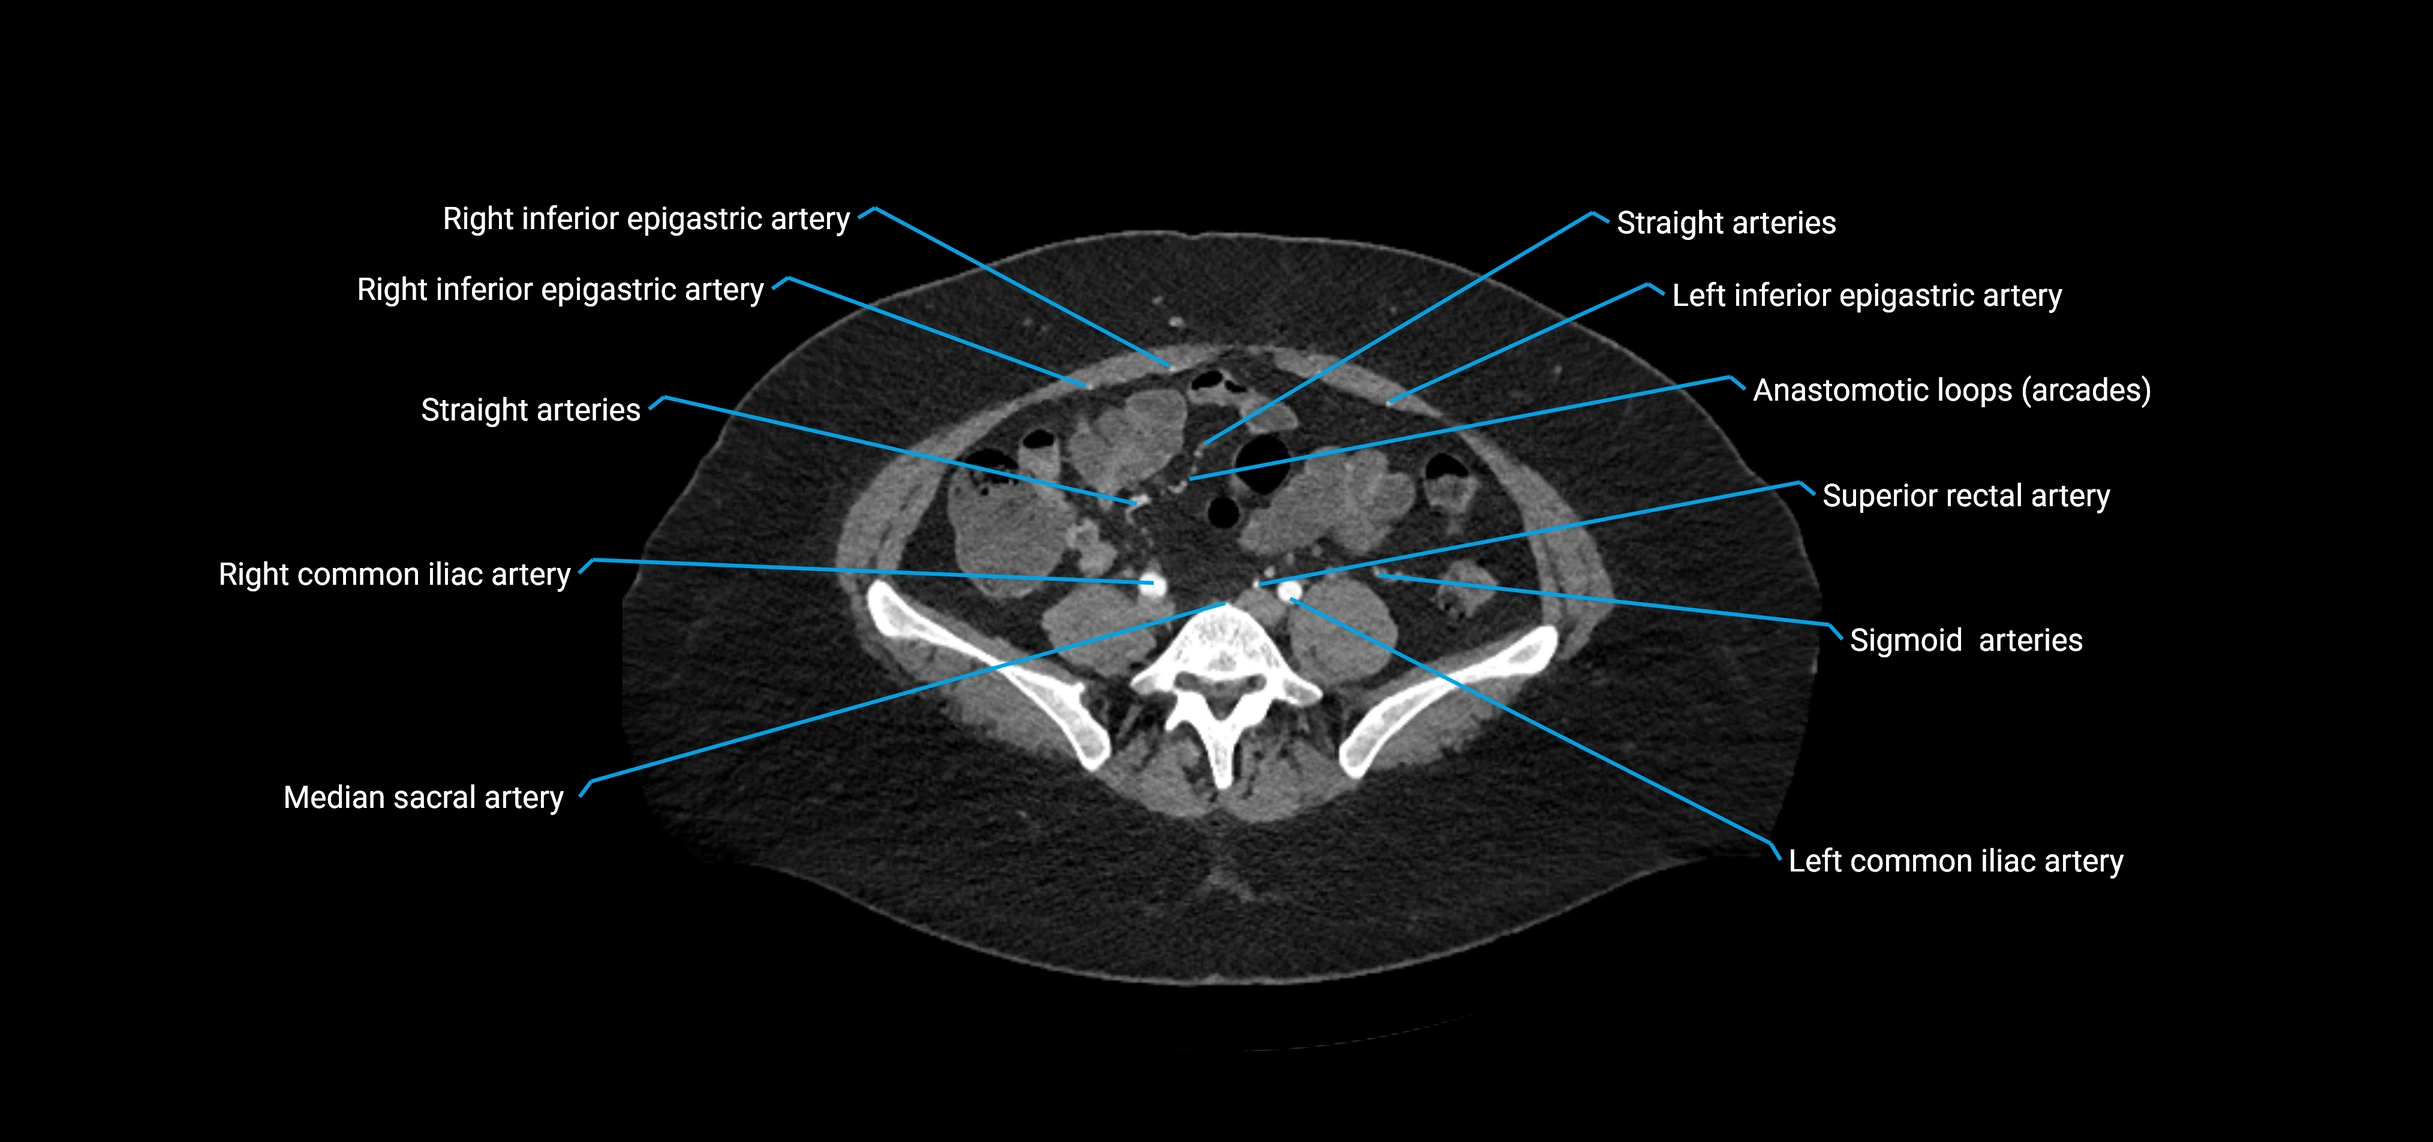

Contrast-enhanced CT (CTA):

• Gold standard for abdominal aortic imaging

• Provides excellent detail of lumen, wall, aneurysm, thrombus, and branch vessels

• Multiplanar and 3D reconstructions help in aneurysm measurement, stent graft planning, and dissection evaluation